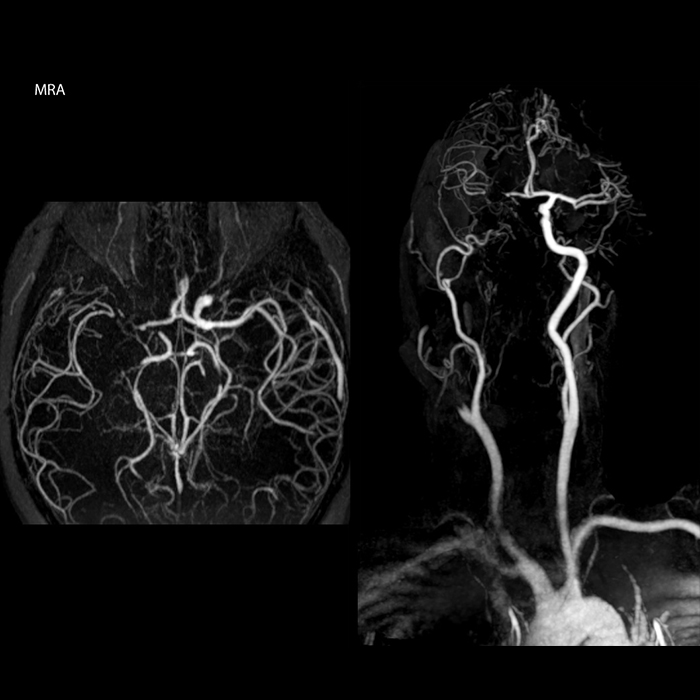

“In France, stroke is usually imaged with MRI, not CT, even for emergency treatment. This is because MRI helps us directly visualize ischemia in the acute phase, but can also help rule out differentials such as MS and hematoma. In addition, we can assess the intracranial and extracranial vessels during the same examination,” says Dr. Savatovsky.

“Ingenia provides great flexibility in the parameters setting. We can tune a sequence the way we want,” says Dr. Savatovsky. “For example, in a stroke exam we use a FLAIR sequence of about two minutes instead of the four-minute FLAIR we use for MS. The diffusion is 30 seconds, the T2*-weighted scan is 30 seconds, the angiography scan time is less than one minute. Ingenia is a great scanner in that situation; even with these fast sequences we can achieve good images with good SNR. When the first sequence tells us that it’s not an ischemic stroke but a hemorrhagic stroke, we may switch to a time-resolved angiography to look for vascular malformations and venous thrombosis.

The ideal stroke protocol?

“Every center is different, but for me the ideal protocol for stroke includes diffusion weighted imaging, FLAIR, and fast susceptibility imaging,” says Dr. Savatovsky. “Our fast susceptibility weighted imaging takes 50 seconds, so it’s as fast as T2*-weighted imaging. It visualizes hemorrhage but also the clots. We also do 3D MR angiography that provides information on cervical and brain vessels. If the patient does not need immediate treatment, or if additional information is needed to decide on treatment, we might also add perfusion imaging and post-contrast T1-weighted imaging.”